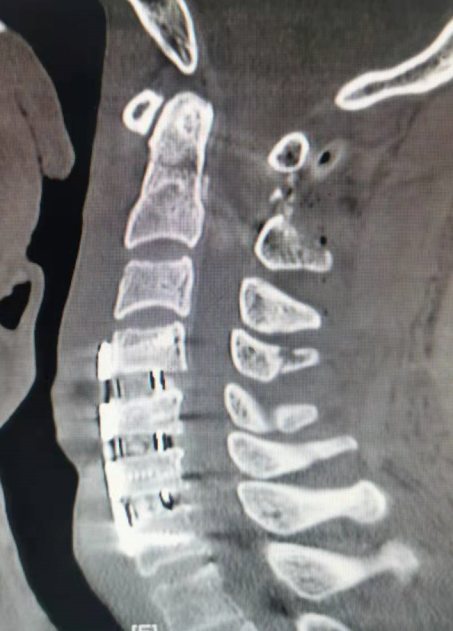

朱希田副主任医师组织科室医护团队进行了详细的讨论分析,决定先予俯卧位行“后入路寰枢椎骨折切开复位+椎弓根钉内固定术”,再仰卧位行“前入路颈4-5、颈5-6、颈6-7椎间盘切除+颈椎管减压+颈椎椎间植骨融合+颈4-颈7椎体钛板螺钉内固定手术”。

凭借娴熟的手术技术,医生成功地在复杂的寰枢椎上置入椎弓根螺钉,并将脱位的齿状突骨折和寰椎完全复位,成功实现了精准置钉和完全复位,且手术创伤小,出血少,在小切口下顺利完成;前路多节段颈椎手术也很顺利,前路+后路手术出血仅100-200ml。术后患者很快恢复清醒,四肢开始活动,术后8小时开始进流质饮食,术后第3天便可下地行走,之后各项生活逐渐恢复自理。